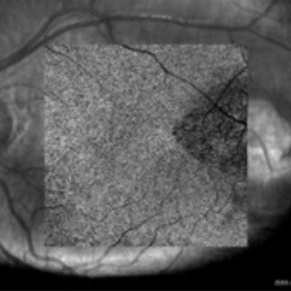

IR imaging photograph of an asymptomatic 12-year-old girl with torpedo maculopathy of the left eye.

Photographer: Pierre-Henry Gabrielle, Ophthalmology department, Dijon University Hospital, France

Imaging device: Heidelberg Spectralis

Condition/keywords: infrared image, torpedo maculopathy